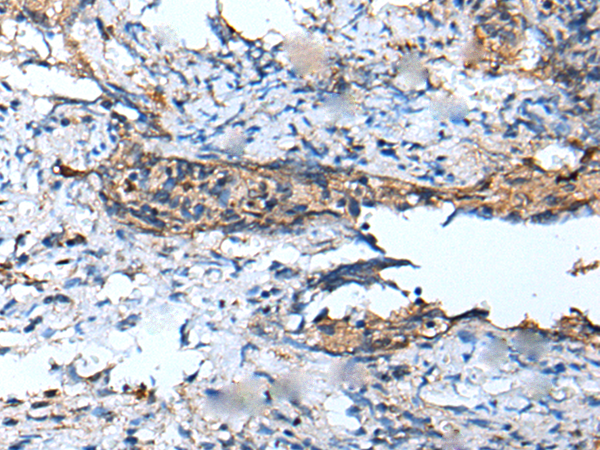

IHC (Immunohiostchemistry)

(The image on the left is immunohistochemistry of paraffin-embedded Human cervical cancer tissue using DEFB104A Antibody at dilution 1/100, on the right is treated with synthetic peptide. (Original magnification: x200))

IHC (Immunohistochemistry)

(The image on the left is immunohistochemistry of paraffin-embedded Human tonsil tissue using DEFB104A Antibody at dilution 1/100, on the right is treated with synthetic peptide. (Original magnification: x200))